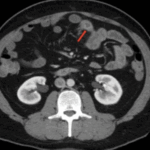

Malignant Tumors of the Small Intestine: A Case Series and Review of the Literature

Small bowel neoplasms are uncommon gastrointestinal malignancies, but their incidence has risen in recent years. The main subtypes include adenocarcinoma and neuroendocrine tumors, each accounting for approximately 40% of cases, […]